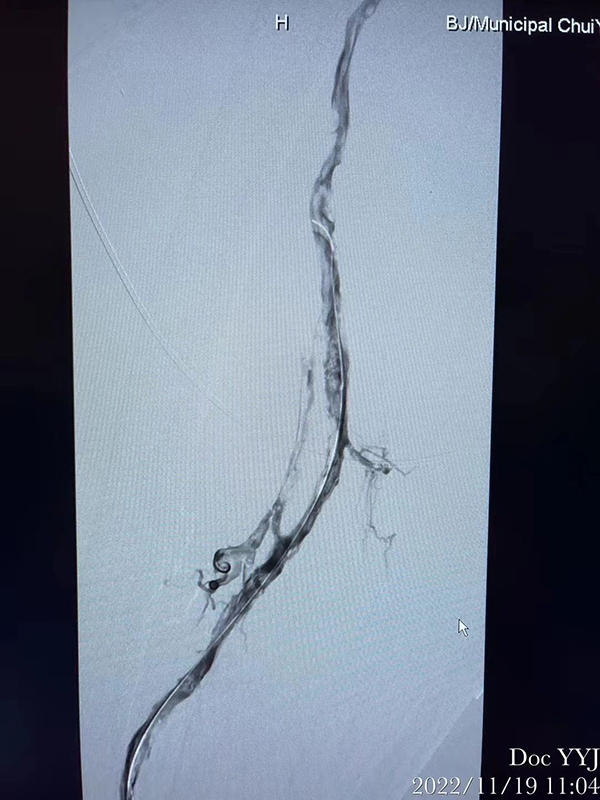

深静脉血栓(DVT):多发生于下肢静脉(尤其腘静脉、股静脉),表现为肢体肿胀疼痛。

首选下肢静脉超声(无创、准确率 > 95%)

怀疑肺栓塞需做 CT 肺动脉造影(CTPA)

分层治疗